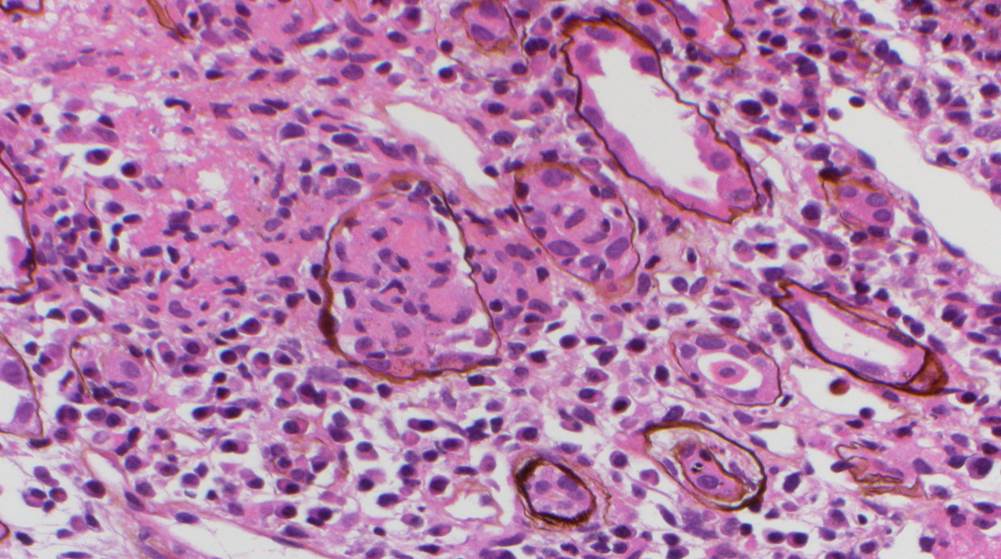

A renal allograft biopsy is essential to differentiate adenoviral nephritis from that of acute rejection or other pathology. Typical light microscopic findings in adenovirus nephropathy include tubular cell necrosis (with tubular basement membrane rupture) associated with severe interstitial inflammation (sometimes with granuloma formation), focal interstitial hemorrhage and viral cytopathic changes including peripheral condensed chromatin, basophilic nuclear inclusions and nuclear enlargement. In some cases such as ours, viral inclusions are not identified, presumably because of the focal nature of viral infection in the kidney. Immunoperoxidase staining can be used to confirm the presence of adenovirus within the nuclei, and to a lesser degree, within the cytoplasm of tubular epithelial cells; although weak, our case showed positive staining. These viral particles are visible under electron microscopy, measuring approximately 75 nm, however they were absent in our patient. Diagnosis in such cases can be clinched by urine examination showing white cell casts and decoy cells, and PCR on the urine testing positive for viral DNA.